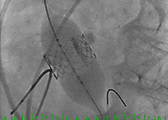

- The valve is deployed in position during direct fluoroscopic visualization (Figure 6) with another brief period of rapid ventricular pacing to reduce ejection. Respirations are also suspended during this period to limit the movement within the thoracic cavity and optimize visualization. Clear communication is critical during this brief period of the procedure and so one person commands the timing of each step of the procedure in a standard clear format.

Figure 6. The valve is deployed in position during direct fluoroscopic visualization with a brief period of rapid ventricular pacing to reduce ejection.